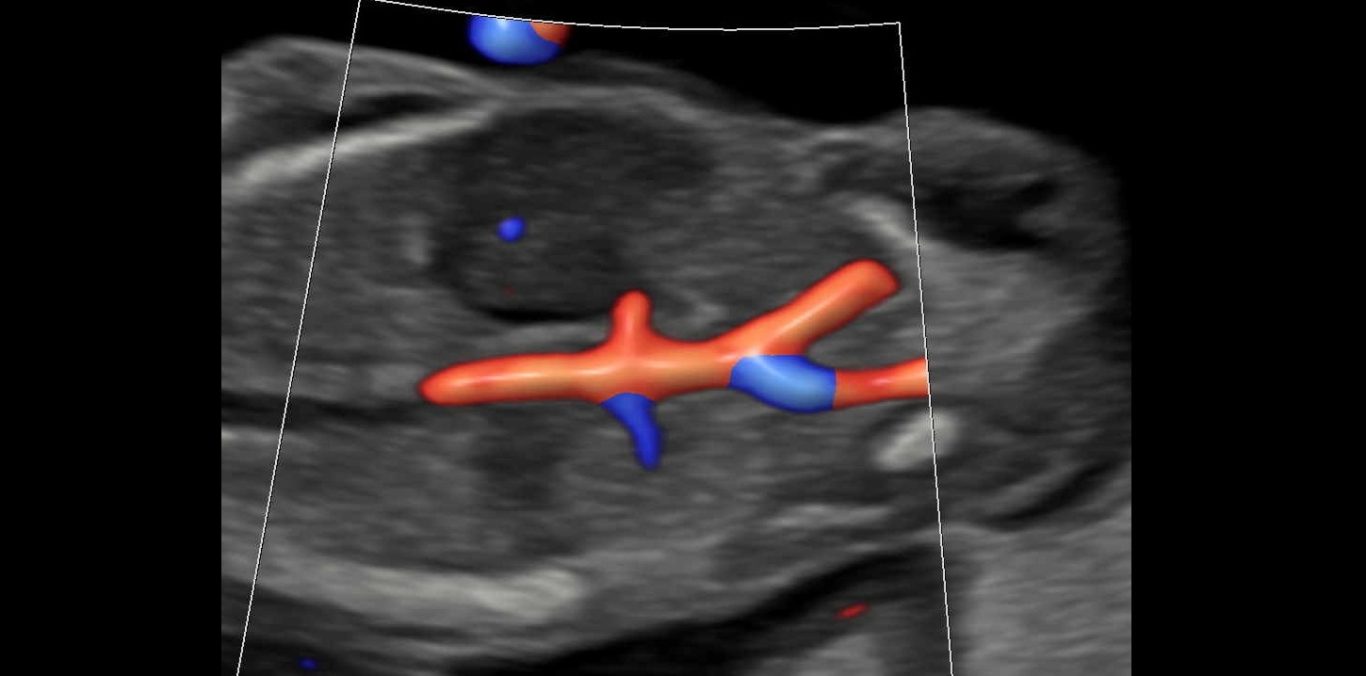

Doppler

Bei dieser Untersuchung messen wir die Durchblutung in der Nabelschnur und anderen Blutgefäßen, um die Versorgung Ihres Kindes zuverlässig einzuschätzen und zu überwachen. Je nach Fragestellung ist diese Untersuchung ab 11 SSW möglich.